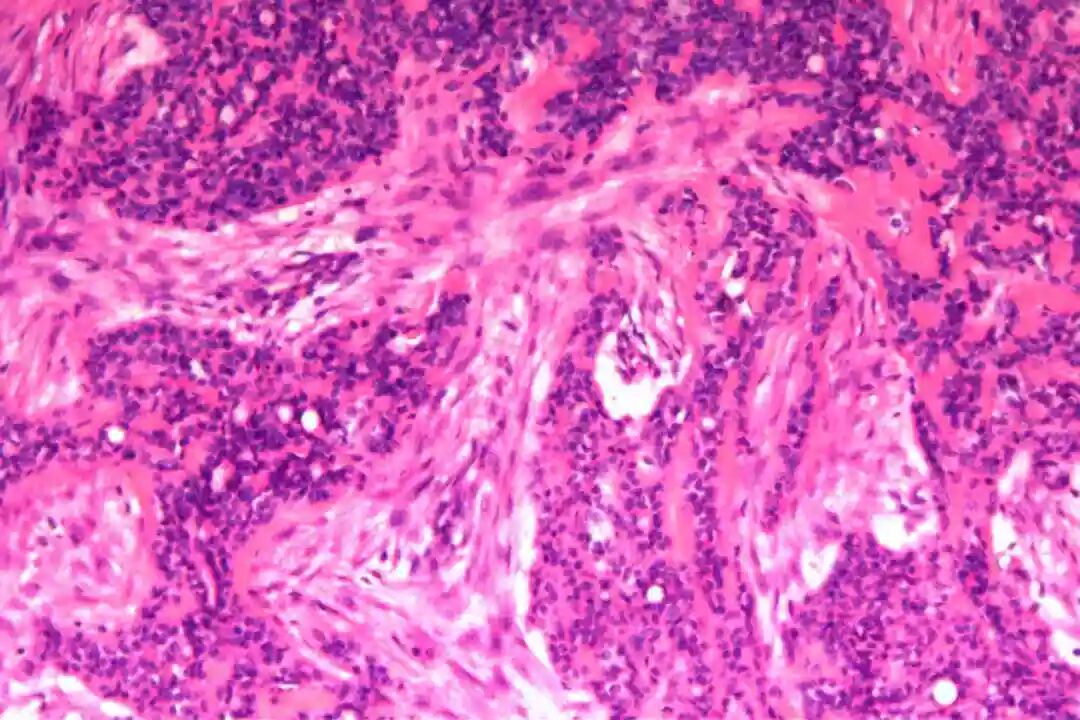

细胞形态:基底样肌上皮细胞体积较小,呈圆形或卵圆形,细胞核深染、染色质均匀,核仁不明显,胞质稀少、淡嗜酸性;腺上皮细胞体积略大,呈柱状或立方状,细胞核淡染、染色质疏松,核仁清晰,胞质丰富、嗜酸性。实性巢团内可见少量微小腔隙,腔隙内可含有少量嗜酸性或嗜碱性黏液样物质(PAS染色阳性),这是实体型与其他实性肿瘤的重要鉴别点;核分裂象少见,一般≤5个/10HPF,部分实体型区域可出现轻度至中度细胞异型性,但无明显恶性增殖活性表现,与高级别乳腺癌的细胞异型性有明显区别。

实体型区域与经典型区域无明显明确界限,相互穿插分布,实体型巢团可逐渐过渡为经典型的筛状或管状结构,两种区域的细胞成分相互延续,均可见腺上皮细胞与肌上皮细胞的混合存在,无明显细胞异型性差异(实体型区域异型性略高于经典型,但整体温和)。这种混合性形态是本病的重要镜下特点,也是与单纯实体型PACC、单纯经典型PACC的主要区别。

病理诊断:(左)乳腺:符合腺样囊性癌,实体型为主,部分经典型;肿块大小约5.5x4.5x3.2cm,神经见癌侵犯,脉管内未见癌栓;标本上、下、内、外、表面及基底切缘均未见癌;乳头见癌累及。